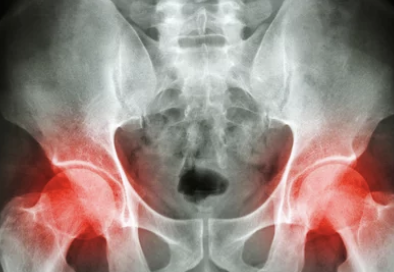

1️⃣ 허리·엉덩이 통증

- 골반이 기울어지면 척추와 요추에 과부하가 걸려 허리 통증 발생

- 오래 앉아 있을 때 허리 뻐근함과 엉덩이 통증 동반

👉 흔히 좌골신경통과 혼동되기도 합니다.